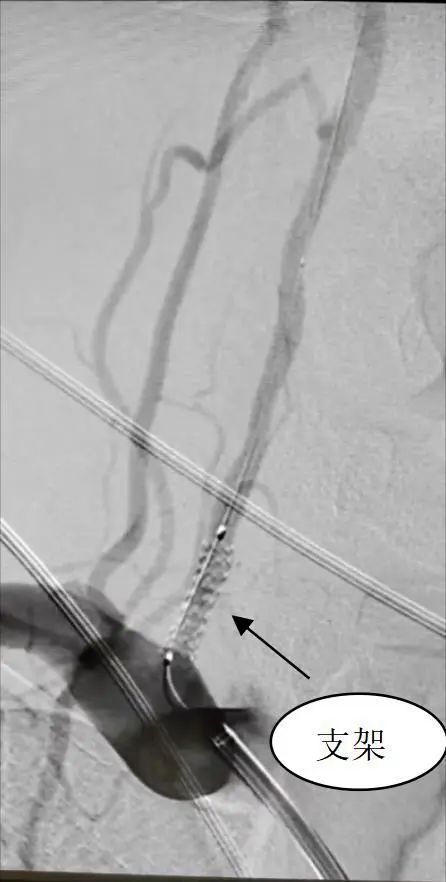

结合老张的情况,单峤带领的介入团队制定了手术方案,双侧颈内动脉闭塞无法挽回,计划实行右侧椎动脉狭窄球囊扩张及支架植入术,保障颅内代偿供血顺畅。

但因老张右侧椎动脉起始处极度狭窄及迂曲,常规方法微导丝难以通过,手术时,单峤果断换用多功能微导管导向,置入长交换微导丝顺利放入球囊扩张支架,再次造影见右侧椎动脉开口处狭窄明显改善,残余狭窄程度<10%,支架位置良好,手术顺利完成。